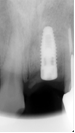

インプラント埋入後X線写真